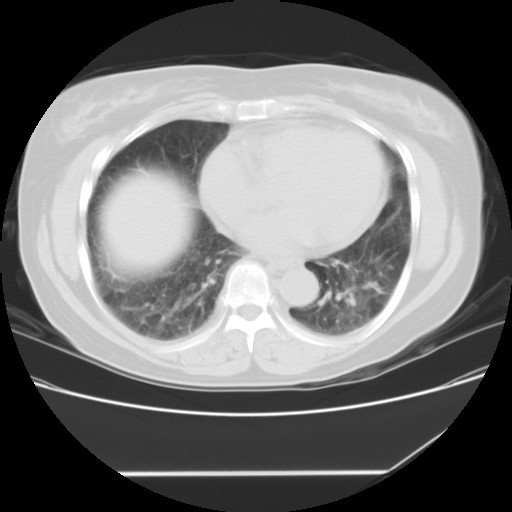

女性,62岁,长期咳嗽,既往从事工作有粉尘接触,有高血压病史,110/150mmhg,近日咳嗽加重,脸面浮肿,请大家帮看下,

1、尘肺;2、慢性支气管炎合并肺部感染;3、心影增大(左房、左室大),考虑高血压性心脏病。

慢支并肺部炎症;右肺结核球?主肺动脉、右肺动脉影不宽,右心室不大,不支持肺心病;无心包积液。

间质性肺炎,有纤维化趋势。

1)慢性支气管炎并肺部感染、肺气肿。2)肺间质纤维化。

间质性肺炎,左下肺机化性肺炎。